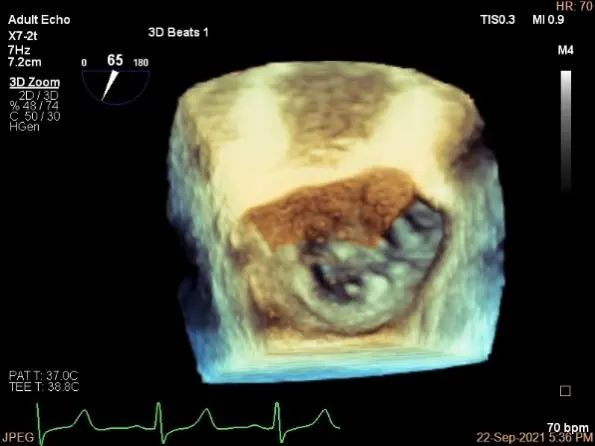

3D:P1区脱垂并腱索断裂,部分AC受累,Width:11.4mm

3D调orientation

3d确认夹子位置在P1区